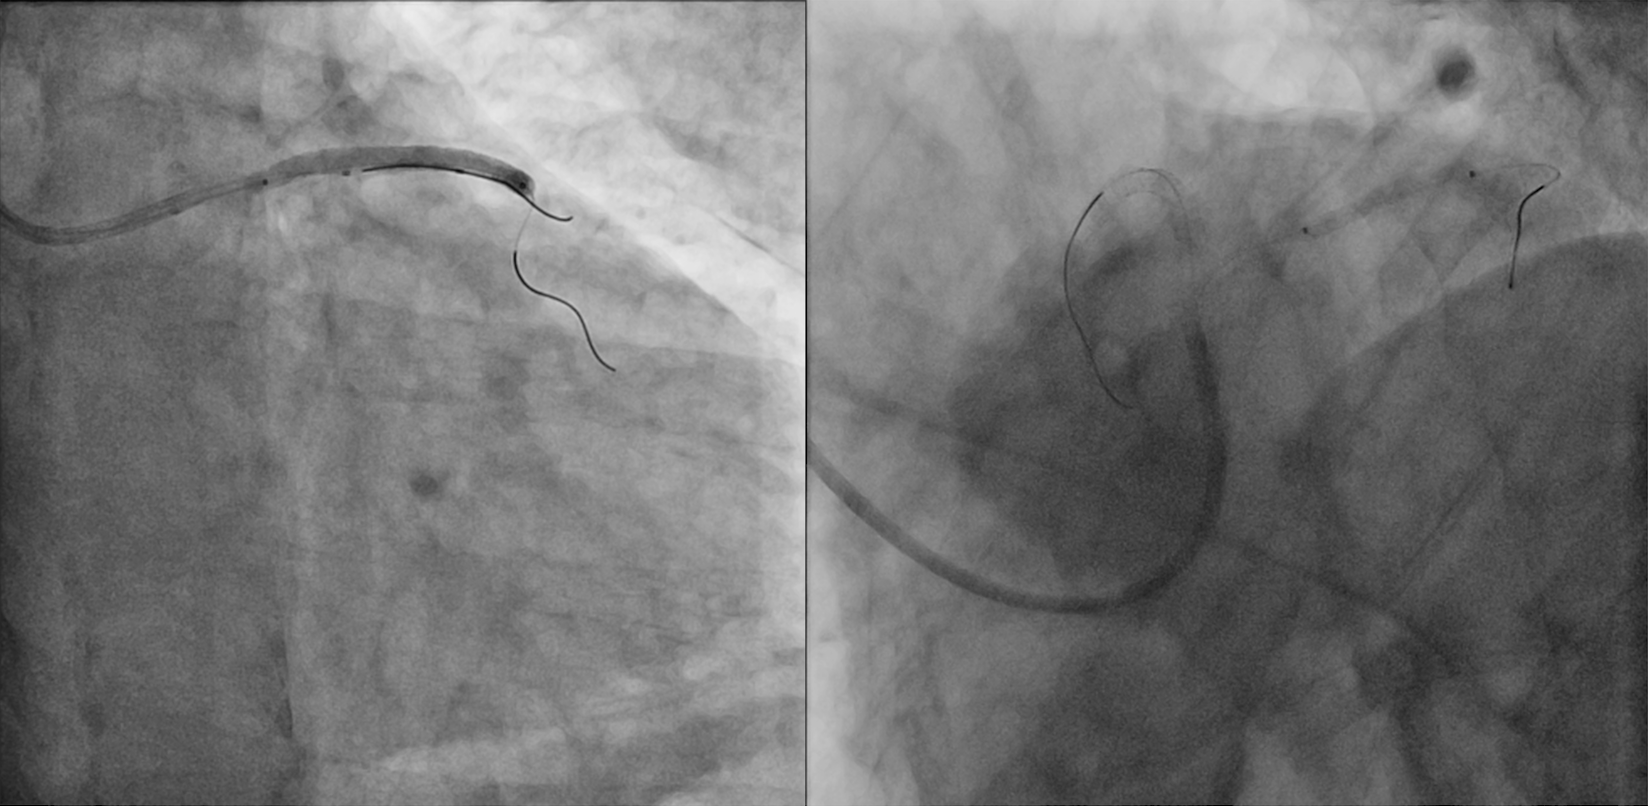

A 75-year-old man was admitted for non-ST-segment elevation myocardial infarction (NSTEMI). Coronary angiography showed focal severe disease at obtuse marginal artery (OM) and severe medina 1,1,1 bifurcation disease involving proximal to middle left anterior descending artery (LAD) and a sizable diagonal branch (Figure 1A, Video 1). With a 6-French extra backup (EBU) 3.5 guide catheter, the LAD was wired with a workhorse guidewire. The diagonal branch had a retroflex takeoff and initial wiring was subintimal (Figure 1B). Parallel wire technique (PWT) with Gaia Next 1 (Asahi Intecc) successfully rewired the true lumen and steered into the distal part of the diagonal branch (Figure 1C, D; Video 2). The LAD was provisionally stented with the diagonal branch protected by jailed balloon technique (JBT) of a 2.0 mm semi-compliant balloon, followed by stenting of the OM (Figure 1E). The final angiographic results were good (Figure 1F, Video 3).